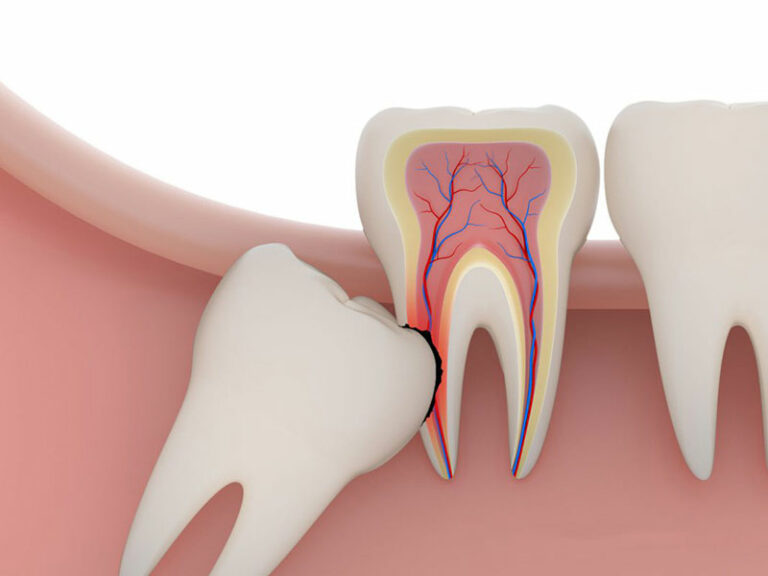

Bác sĩ sẽ tiến hành thăm khám, chụp X – Quang để xác định hình dạng, vị trí và tình trạng xương xung quanh vị trí răng cần nhổ. Từ đó, bác sĩ ước tính mức độ khó của ca tiểu phẫu và hướng nhổ răng hợp lý nhất.